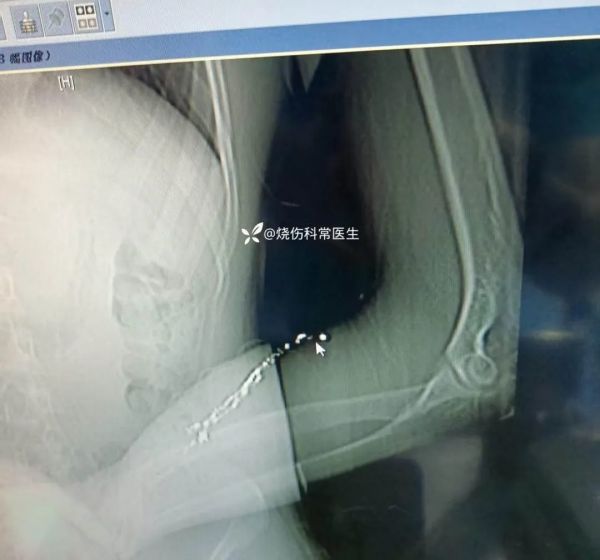

患者信息:男性患者,20 余岁,寻短见自行将体温计内的水银(汞)使用注射器注入左前臂血管中约 5 小时。

检查:入院急查采血化验,肾功、肝功等指标目前没有明确异常。目前只是左前臂肿胀疼痛。

临床诊断:1、前臂血管内异物(汞)。2、汞中毒?

治疗经过及结果:入院检查,通过 X 线和 CT 确定水银具体的位置和深度。